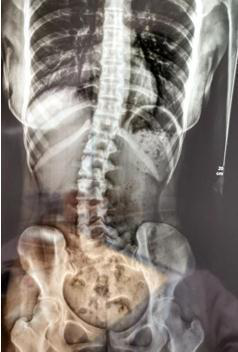

脊柱側(cè)彎的原因有很多,除了先天性原因和特定疾病之外,也由于不正確的姿勢引起的,睡眠姿勢也是其中重要的一部分。

睡姿不當,長時間側(cè)躺睡而且是側(cè)同一邊,并且下腿擺姿不正確。原有正常的脊柱體態(tài)在日積月累的錯誤睡姿中逐漸失衡,骨盆與脊柱位置變化。